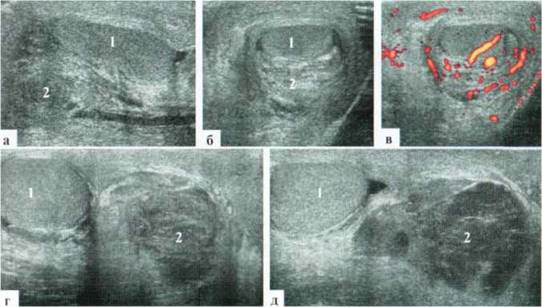

Извитость и/или атипичный ход сосудов семенного канатика при перекруте яичка наблюдается крайне редко. В некоторых случаях имеет место резко выраженный отек придатка и умеренное скопление жидкости в оболочках яичка. Размеры придатка могут практически достигать размеров яичка, контуры его выглядят неровными, структура — гетерогенная (рис. 2.6.2).

Рис. 6.2. Перекрут яичка и придатка у ребенка 12 лет: 1 — яичко; 2 — придаток

После деторсии яичка в случаях его сомнительной жизнеспособности по данным операционной ревизии, УЗИ целесообразно провести на следующие сутки. Появление сосудистого рисунка в паренхиме яичка даже на фоне значительных изменений его структуры оставляет некоторую надежду на восстановление его функции, но, к сожалению, отнюдь ее не гарантирует (рис. 2.6.3).

Рис. 2.6.3. Состояние после оперативной деторсии слева. Сосудистый рисунок в паренхиме яичка восстановился, но имеются выраженные изменения структуры яичка и сохраняется его шаровидная форма

При эхографичсской оценке состояния яичка после деторсии очень помогает сравнительная визуализация обоих яичек ребенка в режиме «двух полей» как в В-режиме, так и в режиме цветового допплера.

Собственный опыт заставляет с осторожностью прогнозировать сохранность функционального состояния таких яичек: наблюдение в динамике выявляет постепенное уменьшение их в размере, хотя сосудистый рисунок в паренхиме остается сохраненным (рис. 2.6.4).

Рис. 2.6.4. Динамическое эхографическое наблюдение над мальчиком 13 лет после деторсии слева: а, 6— через 2 суток после деторсии; в, г — через месяц после деторсии